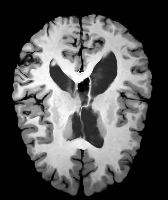

Moving Target Mono-0 Mono-5 DA-1 DA-5 Mono-200 Refer to caption Refer to caption Refer to caption Refer to caption Refer to caption Refer to caption Refer to caption Refer to caption Refer to caption Refer to caption Refer to caption Refer to caption Refer to caption Refer to caption

Image Manual Seg DA-1 Mono-21 DA-21 Mono-65 Refer to caption Refer to caption Refer to caption Refer to caption Refer to caption Refer to caption

Figure 2:  Examples of knee MRI registration (top) and brain MRI segmentation (bottom) results. Top: The first two columns are the moving image/segmentation and the target image/segmentation followed by the warped moving images (with deformation grids)/segmentations by different models. Bottom left to right: original image, manual segmentation, and predictions of various models. Mono-i𝑖i and DA-i𝑖i represent the mono- and DA models with i𝑖i manual segmentations respectively.

Results: All trained networks are evaluated using Dice overlap scores between predictions and the manual segmentations for the segmentation network, or between the warped moving segmentations and the target segmentations for the registration network. Tabs. 1 and 2 show results for the knee and brain MRI experiments respectively in Dice scores (%). Fig. 2 shows examples of knee MRI registrations and brain MRI segmentations.

Qualitative results: DA achieves more anatomically consistent registrations than the mono-networks on the knee (Fig. 2) and Brain MRI samples (see supplementary material).

Moving Target Mono-0 Mono-21 DA-1 DA-21 Mono-65 Refer to caption Refer to caption Refer to caption Refer to caption Refer to caption Refer to caption Refer to caption Refer to caption Refer to caption Refer to caption Refer to caption Refer to caption Refer to caption Refer to caption

Image Manual Seg DA-1 Mono-5 DA-5 Mono-200 Refer to caption Refer to caption Refer to caption Refer to caption Refer to caption Refer to caption

Figure 4: Examples of brain MRI registration (top) and knee MRI segmentation (bottom) results. Top: The first two columns are the moving image/segmentation and the target image/segmentation followed by the warped moving images/segmentations by different models. Bottom left to right: original image, manual segmentation, and predictions of various models. Mono-i𝑖i and DA-i𝑖i represent the mono- and DA models trained with i𝑖i manual segmentations respectively.